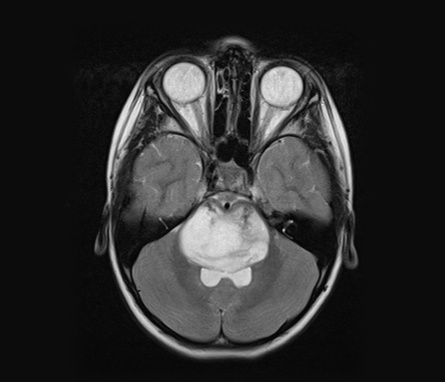

This groundbreaking form of personalized cancer immunotherapy has had remarkable success — more than 45,000 cancer patients worldwide have been treated with CAR T-cell therapy, extending their lives and, in many cases, delivering complete and sustained remissions.